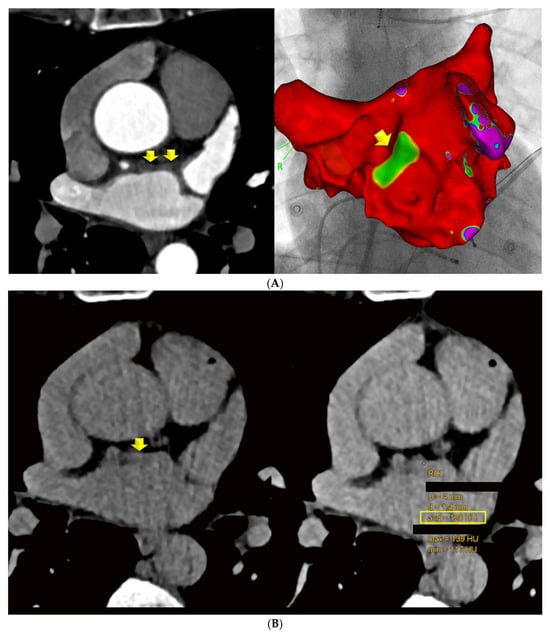

Scan II LE-CT: Axial LE-CT images were co-axially aligned with the CTA datasets on two screens. The left main and proximal left anterior descending (LAD) coronary arteries served as landmarks for co-axial image alignment (Figure 1).

Figure 1. Focal late enhancement (LE). Images (A) of the early phase CTA were co-axially aligned with late enhancement CT performed 7 min after contrast agent injection (B) (2-step CT protocol). (A) LAWT was measured at 3 sites along the LA ridge, and the mean was calculated. The left anterior descending (LAD) coronary artery served as a landmark for co-axial alignment in this patient: a 52-year-old-female with persistent AF, a CVRF of active smoking. The LAWT was >2 mm (A) and focal LE with 130 HU (B) was observed. (C,D) Results in a 54-year-old male with AF prior to planning LA ablation. The mean LAWT was 4 mm (C), and a focal dense spot of late enhancement (LE) was identified at the exact site of maximal LAWT, with 102 HU (D).